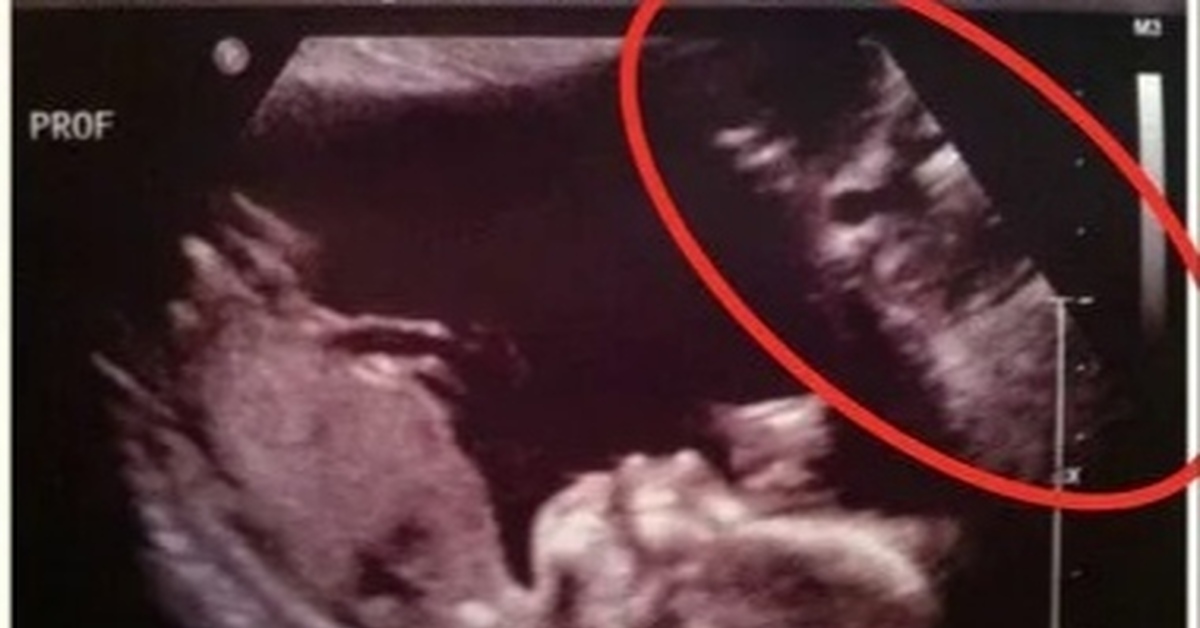

Не сделали узи ребенку

Не сделали узи ребенку 118 фото